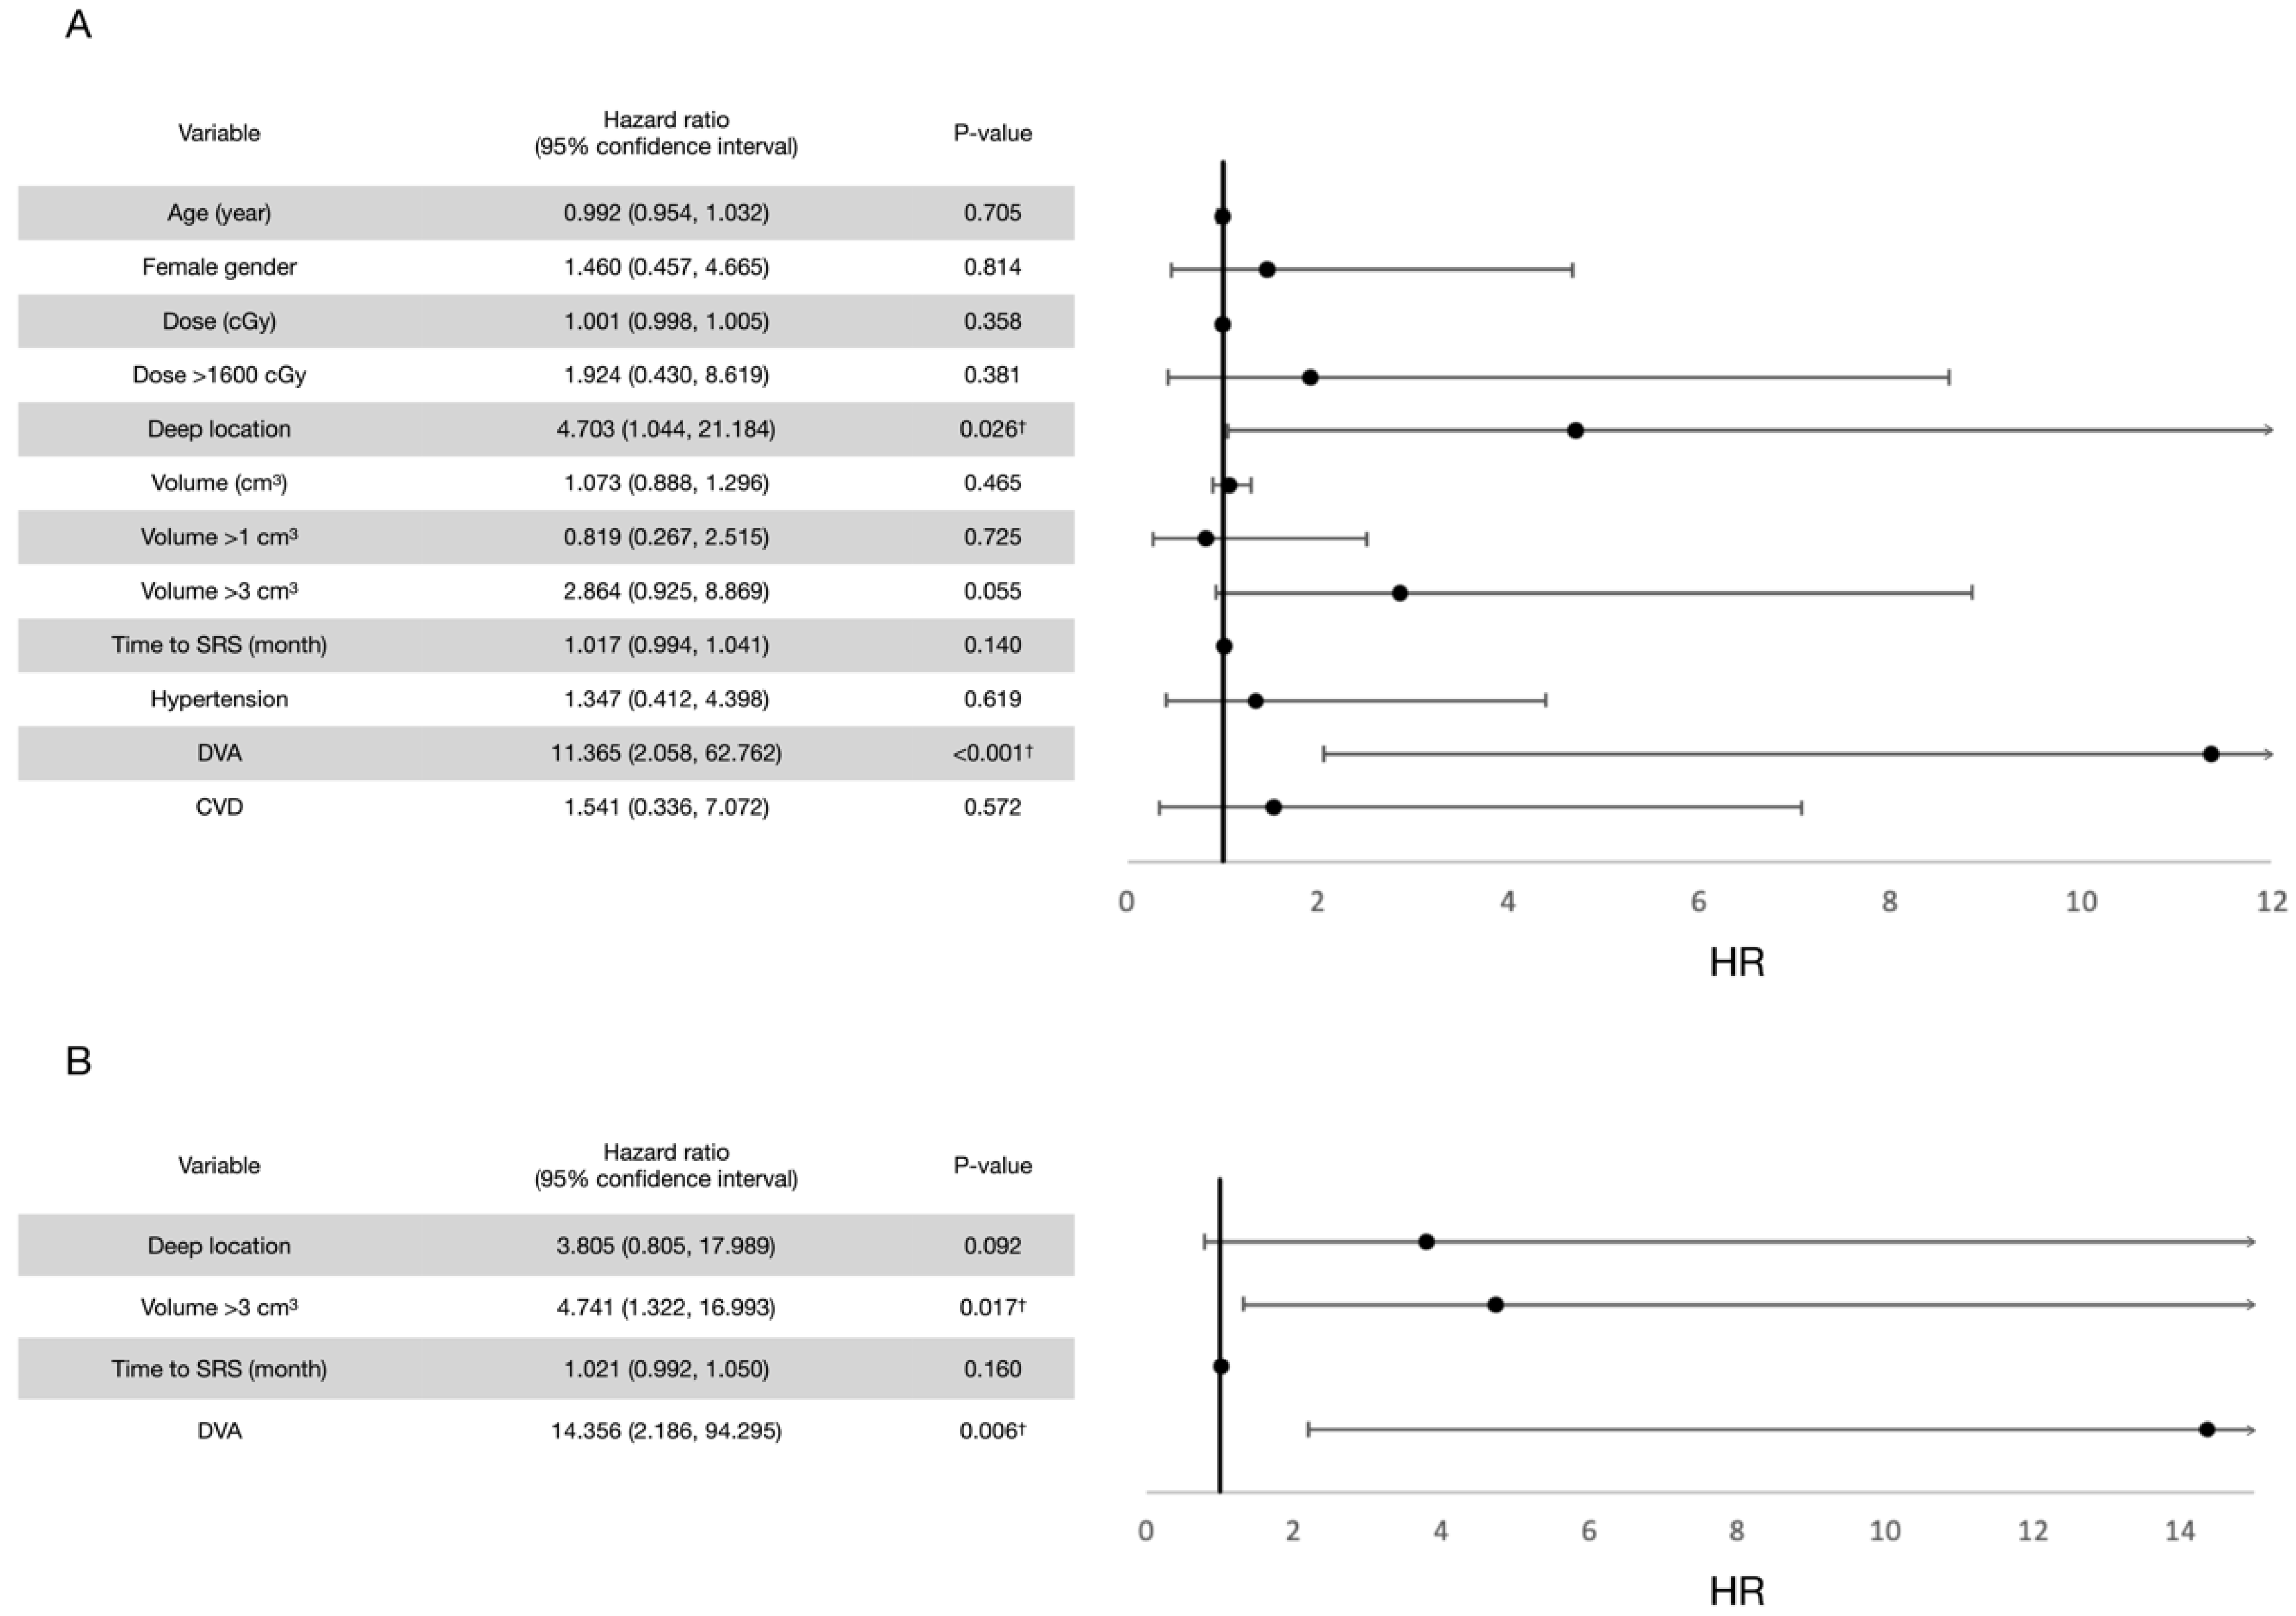

3.2. Post-Radiosurgical Rebleeding Analysis

4.1. Evidence of SRS in Bleeding Control for CCMs